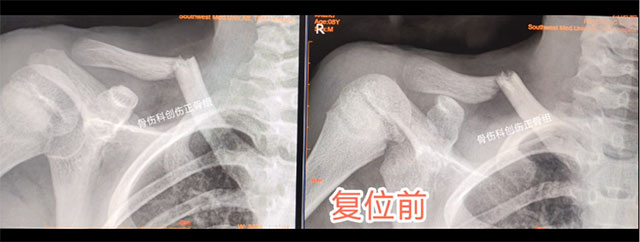

8岁的乐乐同样也是玩耍时不慎摔伤导致右锁骨骨折,来到骨伤科创伤·正骨组就诊,王念武医生同样采用中医正骨手法,小夹板固定治疗,3个月骨折愈合,功能也完全恢复。

术前

术后

根据骨折与脱位的具体情况,进行骨折手法整复,选好适当的小夹板、绷带、棉垫和束带等材料,充分配合骨伤科特制的中药制剂内服及外用治疗,具有复位过程快、固定效果好、疼痛缓解迅速、康复时间短、治疗费用低等优势。